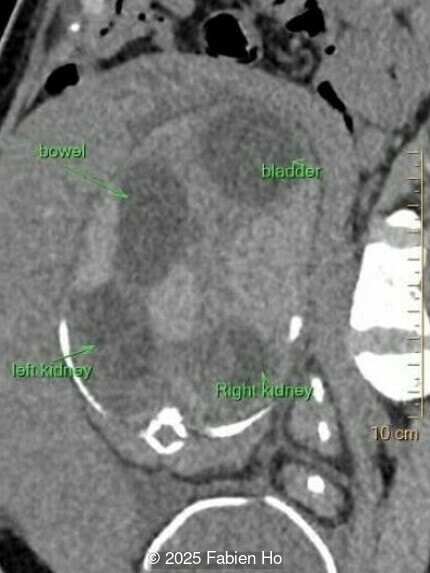

Our prenatal ultrasound revealed a male fetus with megabladder, dilation of both ureter and kidneys, and thinned kidney parenchyma consistent with Lower Urinary Tract Obstruction (LUTO). Additional findings suspected on ultrasound and confirmed on computed tomography included:

- Suspicion of dilated bowel in the left flank, in addition to dilated urinary tract

The diagnosis of PBS is often made in the second trimester of pregnancy, although it has been described as early as 11 weeks of gestation [20]. The most frequent ultrasound findings are a large, thin-walled bladder accompanied by bilateral hydroureter/hydronephrosis, dysplastic kidneys with echogenic renal parenchyma and renal cortical cysts, and abdominal wall laxity which is better viewed after bladder decompression [21]. Cryptorchidism can be detected prenatally by 28 to 30 weeks gestation when the testes descend into scrotum. There may be a patent urachus, visible as a cystic connection between bladder and umbilicus. Oligohydramnios is a frequent finding, which makes it difficult to visualize the associated anomalies.